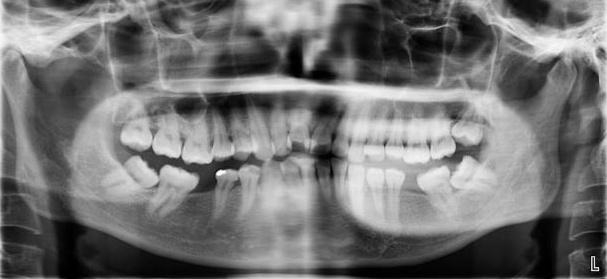

牙齿矫正,其原理就是牙槽骨改建的过程,利用的就是牙齿移动、牙槽骨跟随生长的机制。具体做法就是医生通过矫治器给牙齿施加一个外力,牙齿就会在牙槽骨里缓慢移动,受力侧牙槽骨吸收,受到牵引的一侧牙槽骨增生,以保持牙槽骨正常厚度。此消彼长,所以牙齿是不会松动的。

首先我们看能不能矫正,不是单纯靠年龄来判断,并不是年龄大的就不能矫正,年龄小的就一定能做。限制牙齿移动的关键不是年龄,而是牙周的健康状况。当然,除了牙周的健康程度外,我们还得考虑牙齿的健康程度、关节的健康程度,以及配合度等问题。在排除以上问题后我们还是建议大家尽早解除自己的牙齿问题。